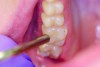

11. Once the sealant is polymerized, evaluate the sealant with an explorer and check for a hard, smooth surface and retention (Figure 11). If necessary, additional sealant can be added if the surface has not been contaminated.

Fig 11. Once the sealant is polymerized, evaluate the sealant with an explorer and check for a hard, smooth surface and retention.

Figure 11